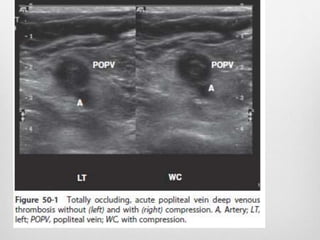

diagnostic criteria for DVT

in Duplex

 Duplex ultrasound diagnostic criteria for DVT

 1.increased intraluminal echogenicity,

 2. increased venous diameter,

 3.inability of the vein to collapse under a moderate

pressure from the transducer,

 4.absence of spontaneous blood flow,

 5. and absence of flow augmentation with distal

compression

Color duplex scan of DVT

 Among these factors, inability to compress the vein

is the most widely used objective criterion for the

diagnosis of DVT.

 limitation of compression ultrasound is its lack of

accuracy in the evaluation of calf veins

 evaluation of venous flow with color Doppler and

spectral Doppler can improve the accuracy of

compression ultrasonography